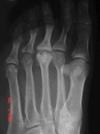

I would really appreciate any advice I can get, because I don't know where to turn. Locals are not very helpful, because they are just not good at judging a good doctor from a bad one. If you are better, the doctor was good; if not, he was bad. They seem to be unaware that doctors are not following any kind of standard routine in dealing with patients, and don't mind a three minute visit with a specialist with other patients standing around in the examination room breathing down your neck. By the way, I am 35 years old, 188cm, and 75 kg, so don't tell me to lose weight! I hope you don't mind if I add my latest x-ray. Perhaps you can see something the doctors don't.

That X-ray is too small for me to read. Could you send me the original scans. Did you digi them with your camera or are the digital X-rays? The lateral and oblique ankle and foot are usually more useful. But there is no substitute for a good physical exam. Is the fixation in the subtalar joint, or the cuboid... the metatarsals etc.

I'm afraid I don't see any signs of Freiberg's disease. I suspect, obviously without examining your foot this is very tentative, you have a case of metatarsalgia second to an old ankle sprain. You can see a bony spur forming in the calcano-cuboid joint, a sure sign of an old untreated injury.